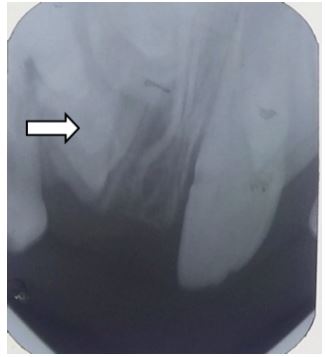

On radiographic investigation, IOPAR (Figure 3) and maxillary occlusal radiograph (Figure 4) revealed well defined radio-opacity superimposing normal radio density of right maxillary central incisor. In addition to above radiographic findings, OPG (Figure 5) also showed that the maxillary right lateral incisor was missing. After assessment of axial and coronal sections of CBCT of maxillary anterior region (Figure 6a, 6b, 6c. 6d, 6e), it was found that there was expansion and thinning of labial cortices of left maxillary central incisor. There was no radiographic evidence of root resorption of adjacent teeth. The root of right central incisor was dilacerated and curved with diffuse periapical rarefaction. At the area of maximum concavity, a well defined radio opaque mass was evident in the midline attached at CEJ of right maxillary central incisor (11) suggestive of odontome attached with the tooth. As a treatment plan, extraction of 11 along with the odontome was advised. After the surgery, the patient was called for follow-up and within a month, partial eruption of left maxiallary central incisor (21) was seen (Figures 8,9).

Figure 3: IOPA reveals well defined Radio-opacity superimposing normal radio density of tooth w.r.t. 11, Incisal edge of 21 above the incisal level of 11 and partially visible 53.